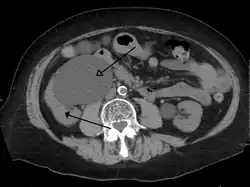

Peripelvic renal cysts may look like hydronephrosis on non-contrast CT (left image). However, CT urography (at right) reveals non-dilated calyces and pelvises.